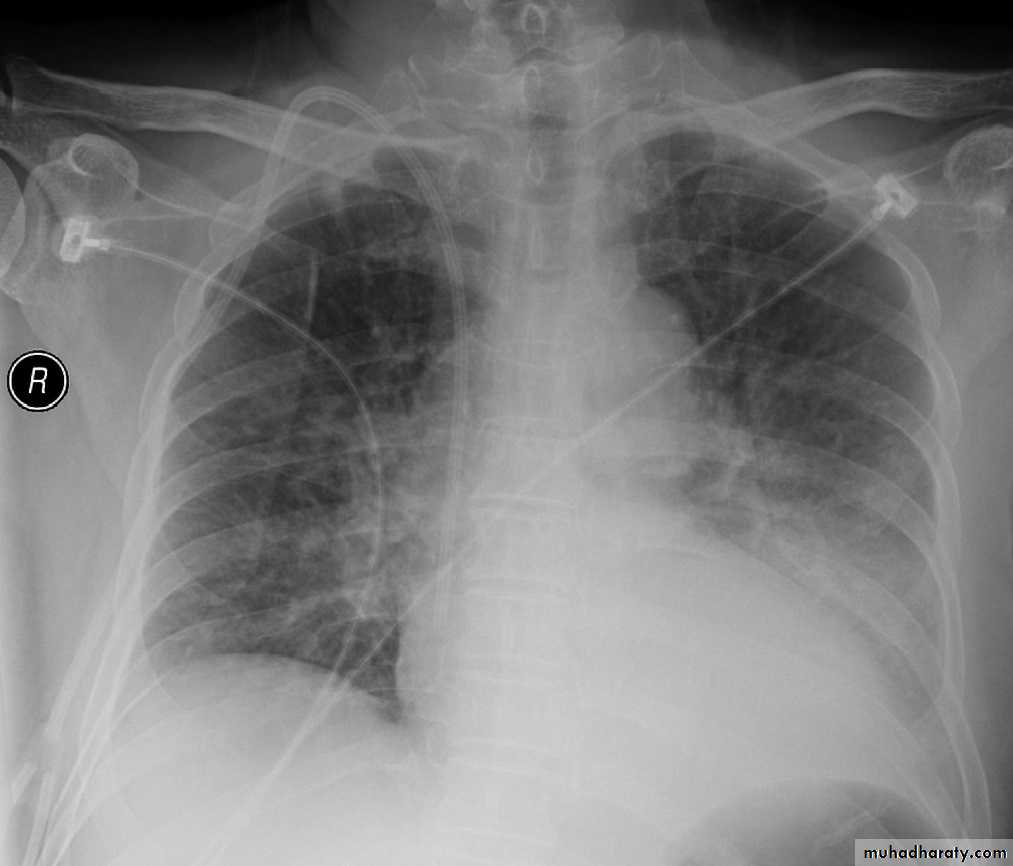

Chest radiography reveals patchy,

often multi-lobar consolidation.

• Chest X Ray